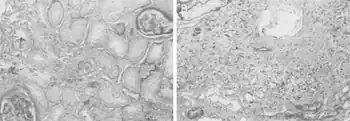

Diagnosis

The diagnosis of this condition can be evaluated based on kidney atrophy, however even kidney status have indicated variable decrease with regards to Balkan endemic nephropathy[15]